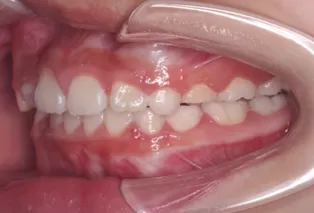

Intraoral photos